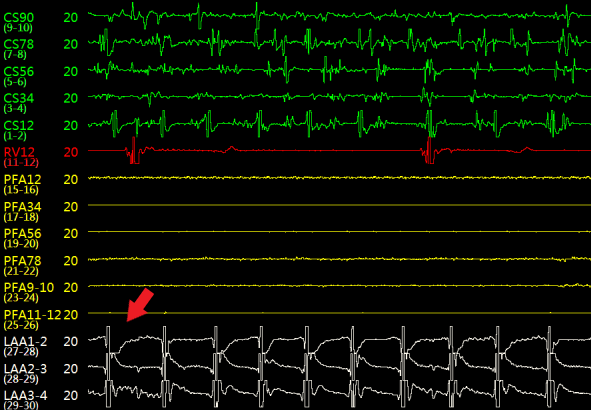

如图3所示,术中造影显示患者的左心耳固定区尺寸为23mm、深度25mm,选用规格为锚定盘直径26mm,密封盘直径 31 mm的左心耳消融封堵器植入到左心耳内。如图4-5所示,消融前后采用德诺电生理标测导管对左心耳进行电信号检测,对比结果表明左心耳电信号完全隔离;如图6所示,术者分别在左心耳消融前后进行了冠状动脉造影,造影显示回旋支无明显变化,无痉挛等不良事件发生;如图7-8所示,封堵器解脱前对左心耳消融封堵器进行了牵拉测试,器械无移位,造影及TEE超声显示左心耳完全封堵,无残余分流。

图4左心耳消融前后左心耳内电位标测

(a)左心耳消融前

(b)左心耳消融后

图5 左心耳消融前后心耳内电位对比,消融后心耳内电位消失